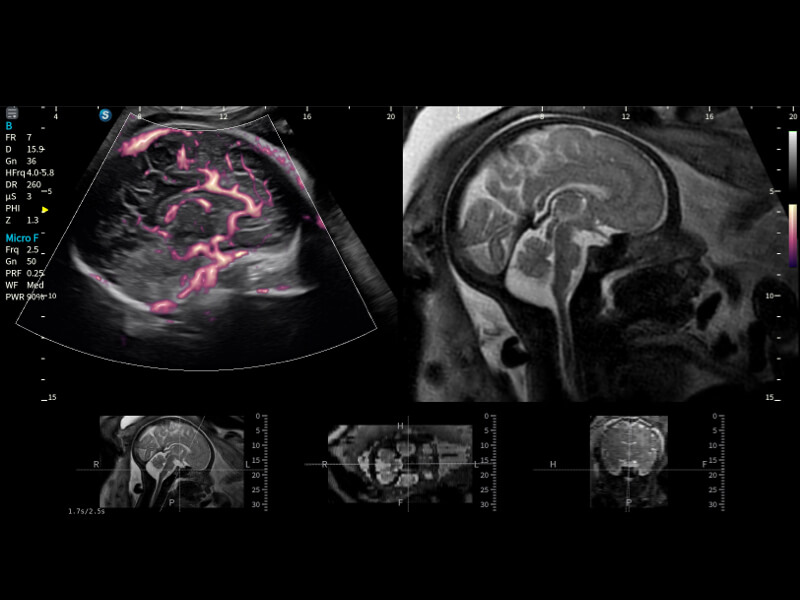

• Micro F

Micro F efficiently distinguishes subtle blood flow signals from overlaying tissue motion, enabling heightened sensitivity and spatial resolution in hemodynamic depiction.

S-Fetus 5.0